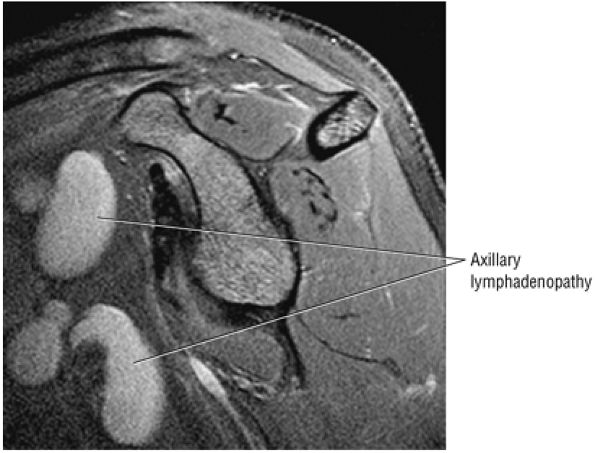

routine shoulder MR examination, when edema and hemorrhage are seen adjacent to the biceps tendon along the proximal humeral shaft. The large arc of muscle bundles making up the deltoid muscle are visualized on axial images anterior, lateral, and posterior to the humeral head and rotator cuff muscles.